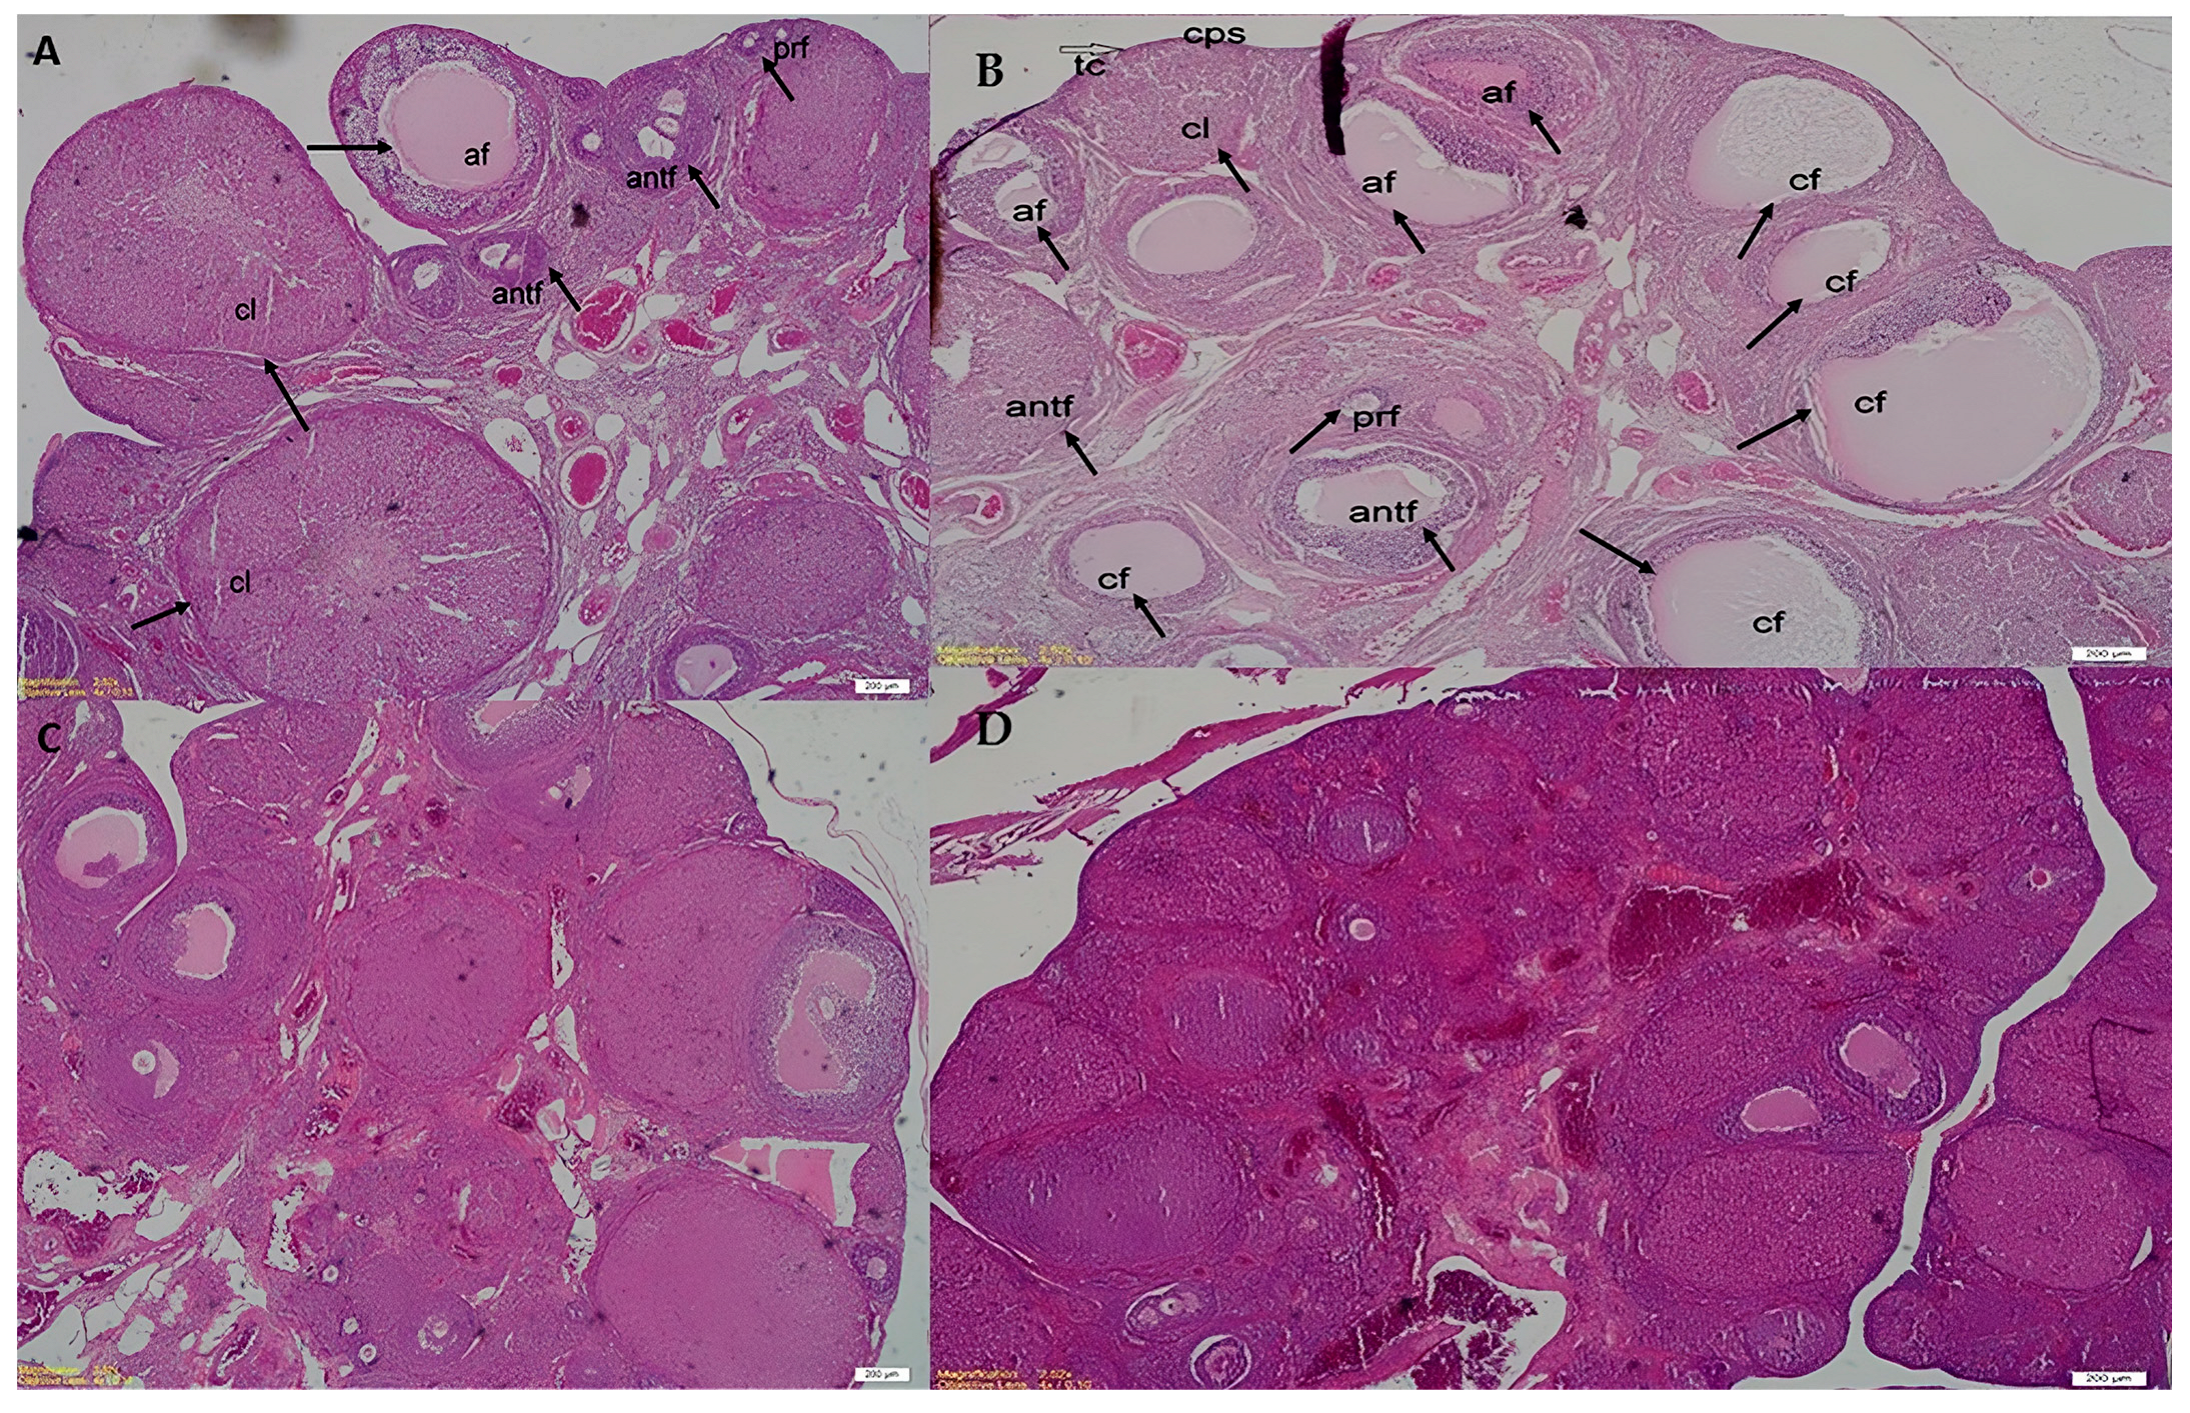

3.2. Histopathological Features

| Preantral Fc | 3.50 ± 0.6 | 2.37 ± 0.4 | 3.11 ± 0.6 | 1.66 ± 0.1 | NS |

| Antral Fc | 6.00 ± 0.7 | 5.25 ± 0.3 | 5.66 ± 0.6 | 6.44 ± 0.6 | NS |

| Atretic Fc | 4.62 ± 0.3 | 6.37 ± 0.7 | 2.22 ± 0.4 | 3.40 ± 0.3 | p < 0.05 (control vs. PCOS); p < 0.001 (PCOS + MET vs. PCOS); p < 0.001 (PCOS + TMQ vs. PCOS) |

| Cystic Fc | 0.5 ± 0.1 | 3.2 ± 0.6 | 0.66 ± 0.2 | 1.11 ± 0.4 | p < 0.01 (control vs. PCOS); p < 0.05 (PCOS + MET vs. PCOS); p < 0.01 (PCOS + TMQ vs. PCOS) |

| Corpus Luteum | 12.88 ± 1.2 | 9.12 ± 1.1 | 14.33 ± 1.3 | 15.00 ± 1.4 | p < 0.05 (control vs. PCOS); p < 0.05 (PCOS + MET vs. PCOS); p < 0.01 (PCOS + TMQ vs. PCOS) |